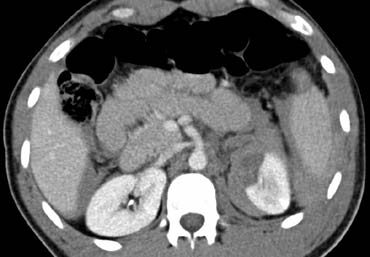

Ca lâm sàng 3

Hình ảnh của bệnh nhân nam 22 tuổi nhập viện 3 giờ sau tai nạn trượt ván tuyết với đau hạ sườn trái và đau vai trái.

Cuộn qua các hình ảnh và mô tả các tổn thương.

Sau đó tiếp tục.

Các dấu hiệu bao gồm:

- Tràn máu ổ bụng quanh lách và gan.

- Vùng giảm tỷ trọng dạng tuyến tính ở phần trước của lách phù hợp với vết rách lách.

- Phía trong của lách có vùng tập trung thuốc cản quang phù hợp với thoát thuốc ngoài mạch.

Như vậy, trong trường hợp này có nguy cơ thất bại của điều trị bảo tồn không phẫu thuật.